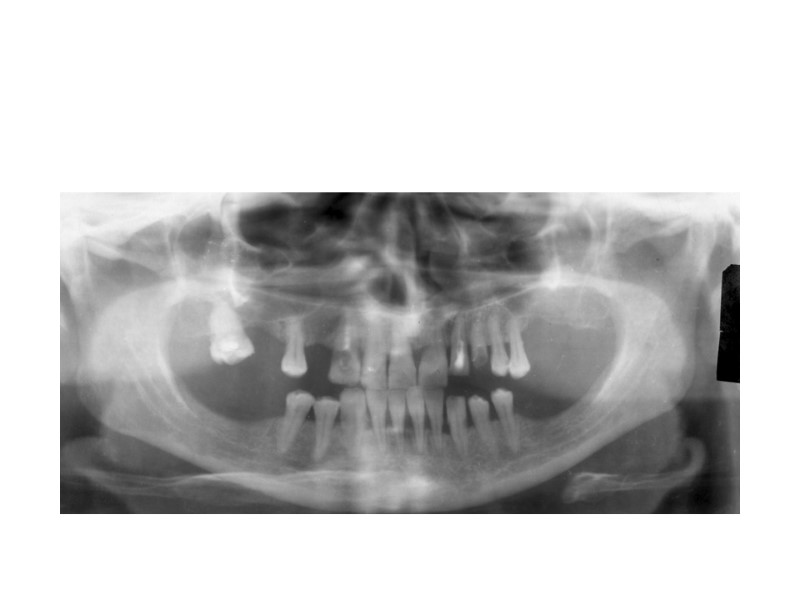

Деструктивный процесс правой ветви нижней челюсти с дополнительным карманом и секвестром в нем

Тотальный деструктивный процесс левой ветви нижней челюсти (одонтогенный остеомиелит)

Одонтогенная киста с ячеистой структурой.